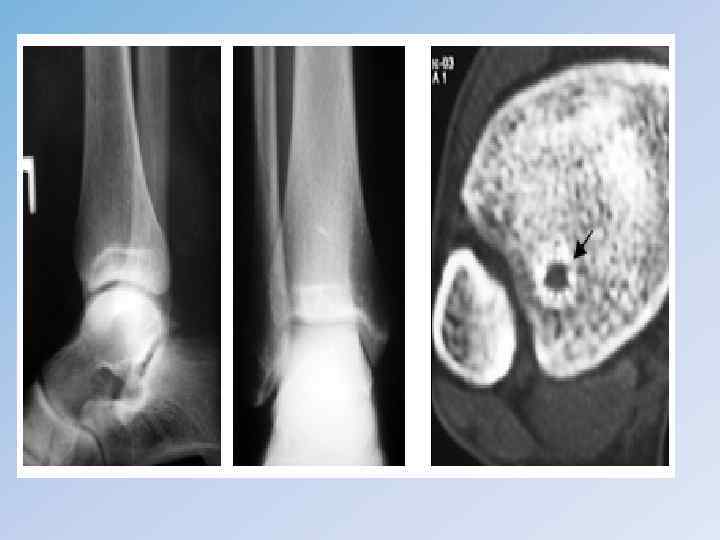

Остеоид-остеома • Остеоид-остеома составляет около 10 % всех доброкачественных опухолей костей, встречается в возрасте от 10 до 25 лет, преимущественно у мужчин. • Основная локализация – диафизы длинных костей, иногда встречается и в костях таза. • Клиника. Для остеоид-остеомы характерны сильные боли в очаге поражения, особенно ночные, боли настолько интенсивные, что порой лишают больных сна. Характерный симптом – стихание болей приеме салициловой кислоты. • Рентгенологически на начальных фазах опухолевый очаг отчетливо различается в виде нечетко очерченного дефекта округлой формы, 1– 2 см в диаметре ( «гнездо» опухоли). Окружающая дефект кость утолщена и склерозирована. На более поздних стадиях дефект заполняется вновь образованной костной тканью. • Гистологически опухоль представлена остеоидной и остеогенной тканью. • Общепринятый метод лечения – радикальное оперативное удаление очага ( «гнезда» опухоли) единым блоком с окружающей полоской склерозированной костной ткани. Выскабливание гнезда не рекомендуется, так как может привести к рецидиву.

• Клиническая картина зависит от локализации – это боли в пораженной конечности, опухоль, нарушение функции. • При пальпации опухоли может ощущаться мелкий хруст, подобно хрусту снега, связанный с множественными мельчайшими переломами истонченного коркового слоя деформированной кости. Нередко наступает патологический перелом. • Рентгенологическая картина : Очаг поражения располагается асимметрично в эпиметафизарной зоне, имеет округлую форму и четко отграничен от неизмененной кости, вплоть до появления склеротического ободка. • Очаг может иметь ячеисто-трабекулярную структуру или вид однородного дефекта кости. Практически всегда наблюдается «вздутие» кости.